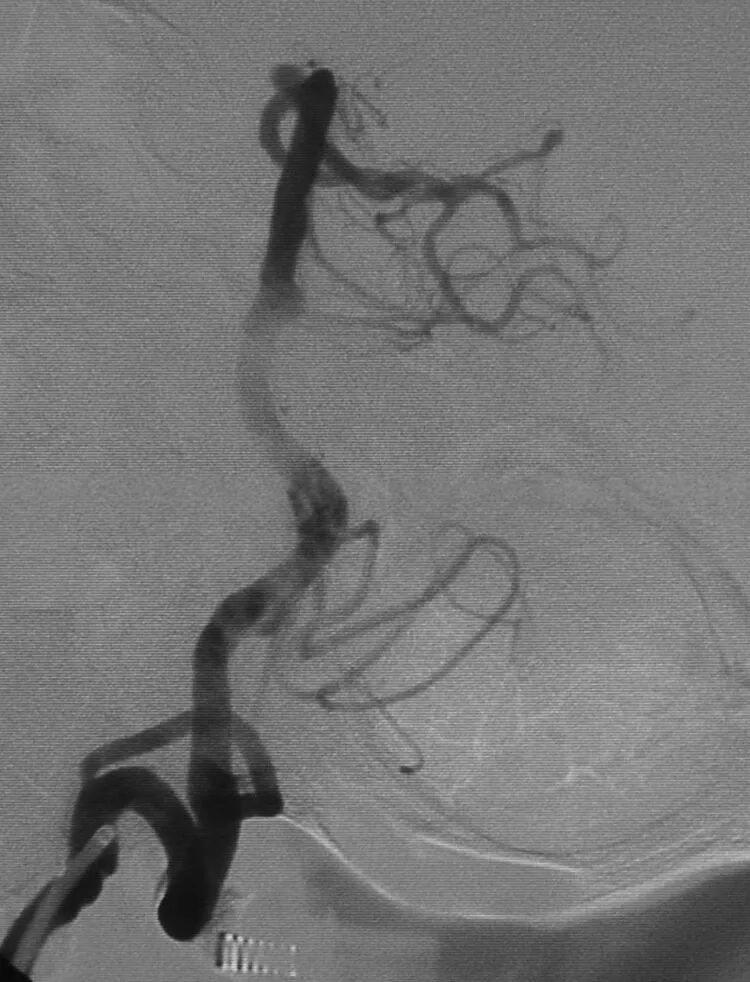

牛角状后交通动脉瘤

使用双微管技术栓塞,两根微导管分别送入动脉瘤的两个分叶,远端分叶角度舒缓,用45度预塑形微导管栓塞;近端分叶成角较锐,把另一根微导管的管头塑成更勾的C形进入近端分叶栓塞之